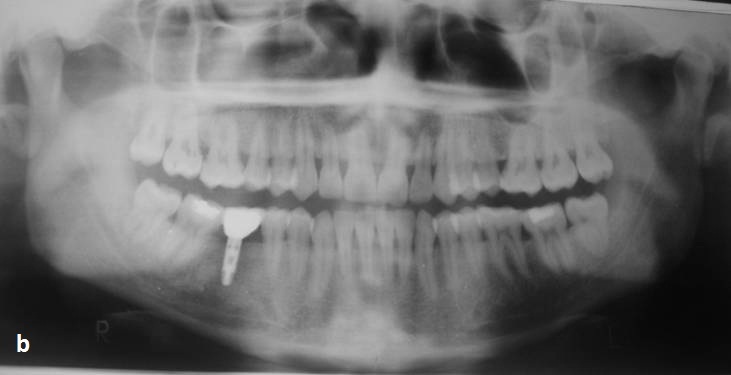

OPG after crown cementation

- OPG after crown cementation